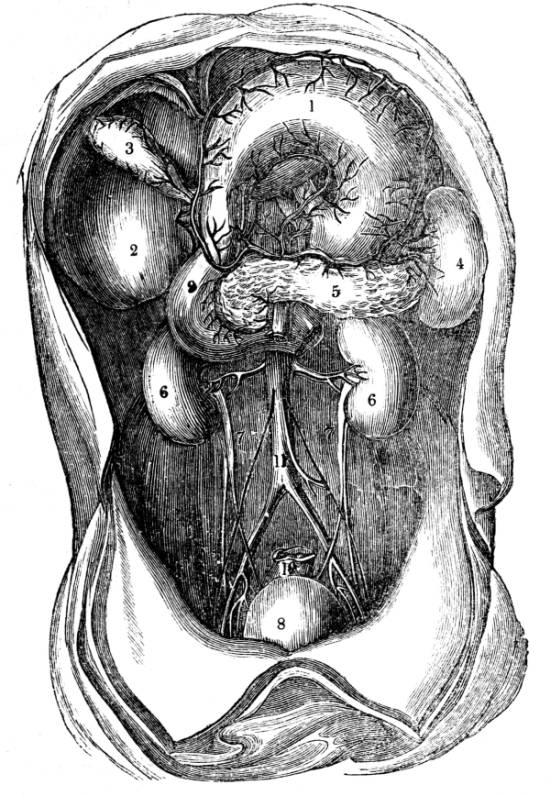

1. The trachea. 2. The right and left bronchus; the left

bronchus showing its division into smaller and smaller

branches in the lung, and the ultimate termination of the

branches in the air vesicles. 3. Right auricle of the heart.

4. Left auricle. 5. Right ventricle. 6. The aorta arising from

the left ventricle, the left ventricle being in this diagram

concealed by the right. 7. Pulmonary artery arising from

the right ventricle and dividing into, 8. The right, and

9. The left branch. The latter is seen dividing into smaller

and smaller branches, and ultimately terminating on the

air vesicles. 10. Branches of one of the pulmonary veins

proceeding from the terminations of the pulmonary artery

on the air vesicles, where together they form the net-work

of vessels termed the Rete Mirabile. 11. Trunk of the

vein on its way to the left auricle of the heart. 12.

Superior vena cava. 13. Inferior vena cava. 14. Air vesicles

magnified. 15. Blood-vessels distributed upon them.

48

371. Such is the structure of the vessel that

carries the air to the blood, and such is the mode

of its distribution.

The vessel that conveys the blood to the air

is the pulmonary artery, the great vessel which

springs from the right ventricle of the heart (fig.

CXL. 5).

The pulmonary artery soon after it issues

from the right ventricle of the heart divides into

two branches (fig. CXL. 7, 8, 9), one for each

lung (fig. CXL. 8, 9). Each branch of the pulmonary

artery as soon as it enters its corresponding

lung (fig. CXL. 9) divides and ramifies

through the organ in a manner precisely similar

to the bronchial tubes. Every branch of the

artery is in contact with a corresponding branch

of the bronchus (fig. CXL. 2), divides as it divides,

and accurately tracks its course throughout (fig.

CXL. 2), until the ultimate divisions of the artery

at length reach the ultimate vesicles of the bronchus

(fig. CXL. 2, 10), upon the delicate walls of

which the capillary arteries rest, expand, and

ramify, forming a net-work of vessels, so complex

that the anatomist who first observed it, named it

the Rete Mirabile, the wonderful net-work, and49

it is still called the Rete Mirabile Malpighi, or

the Rete Vasculosum Malpighi (fig. CXL. 2, 9,

10).